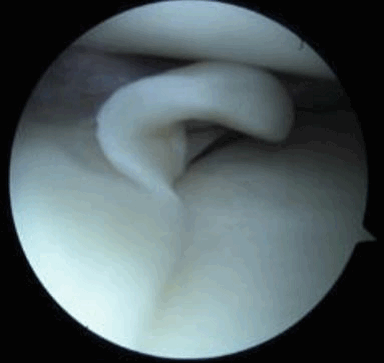

Рис. 1. Схематичное строение менисков

Рис. 2. Эндоскопия коленного сустава. Неповрежденный медиальный мениск. Эндоскопическим способом осматривается свободный край мениска.

Рис. 5. Артроскопическая картина повреждения менисков: а) Лоскутный разрыв тела мениска по типу “собачьего уха”; б) Разрыв-расслоение мениска.